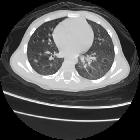

CT - HRCT

The presence of bronchiolitis is best assessed with HRCT. CT features include one of a combination of

- centrilobular micronodules (often seen as tree-in-bud opacities),

- bronchial wall thickening

- bronchiolar dilatation (often referred to as bronchiolectasis)

- mosaic attenuation (and/or air trapping if expiratory imaging is used)